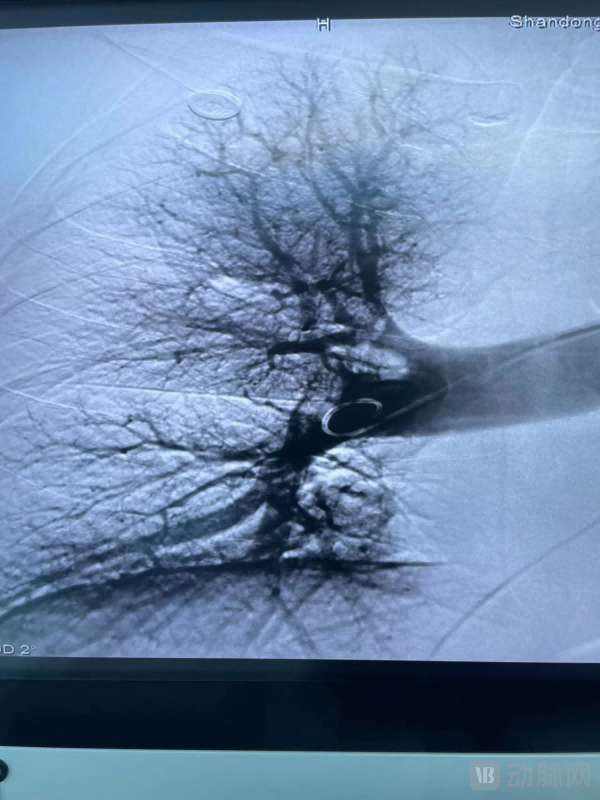

经血管造影确认血栓清除达到目标后结束手术。术后,患者测肺动脉压力明显下降。

术后造影